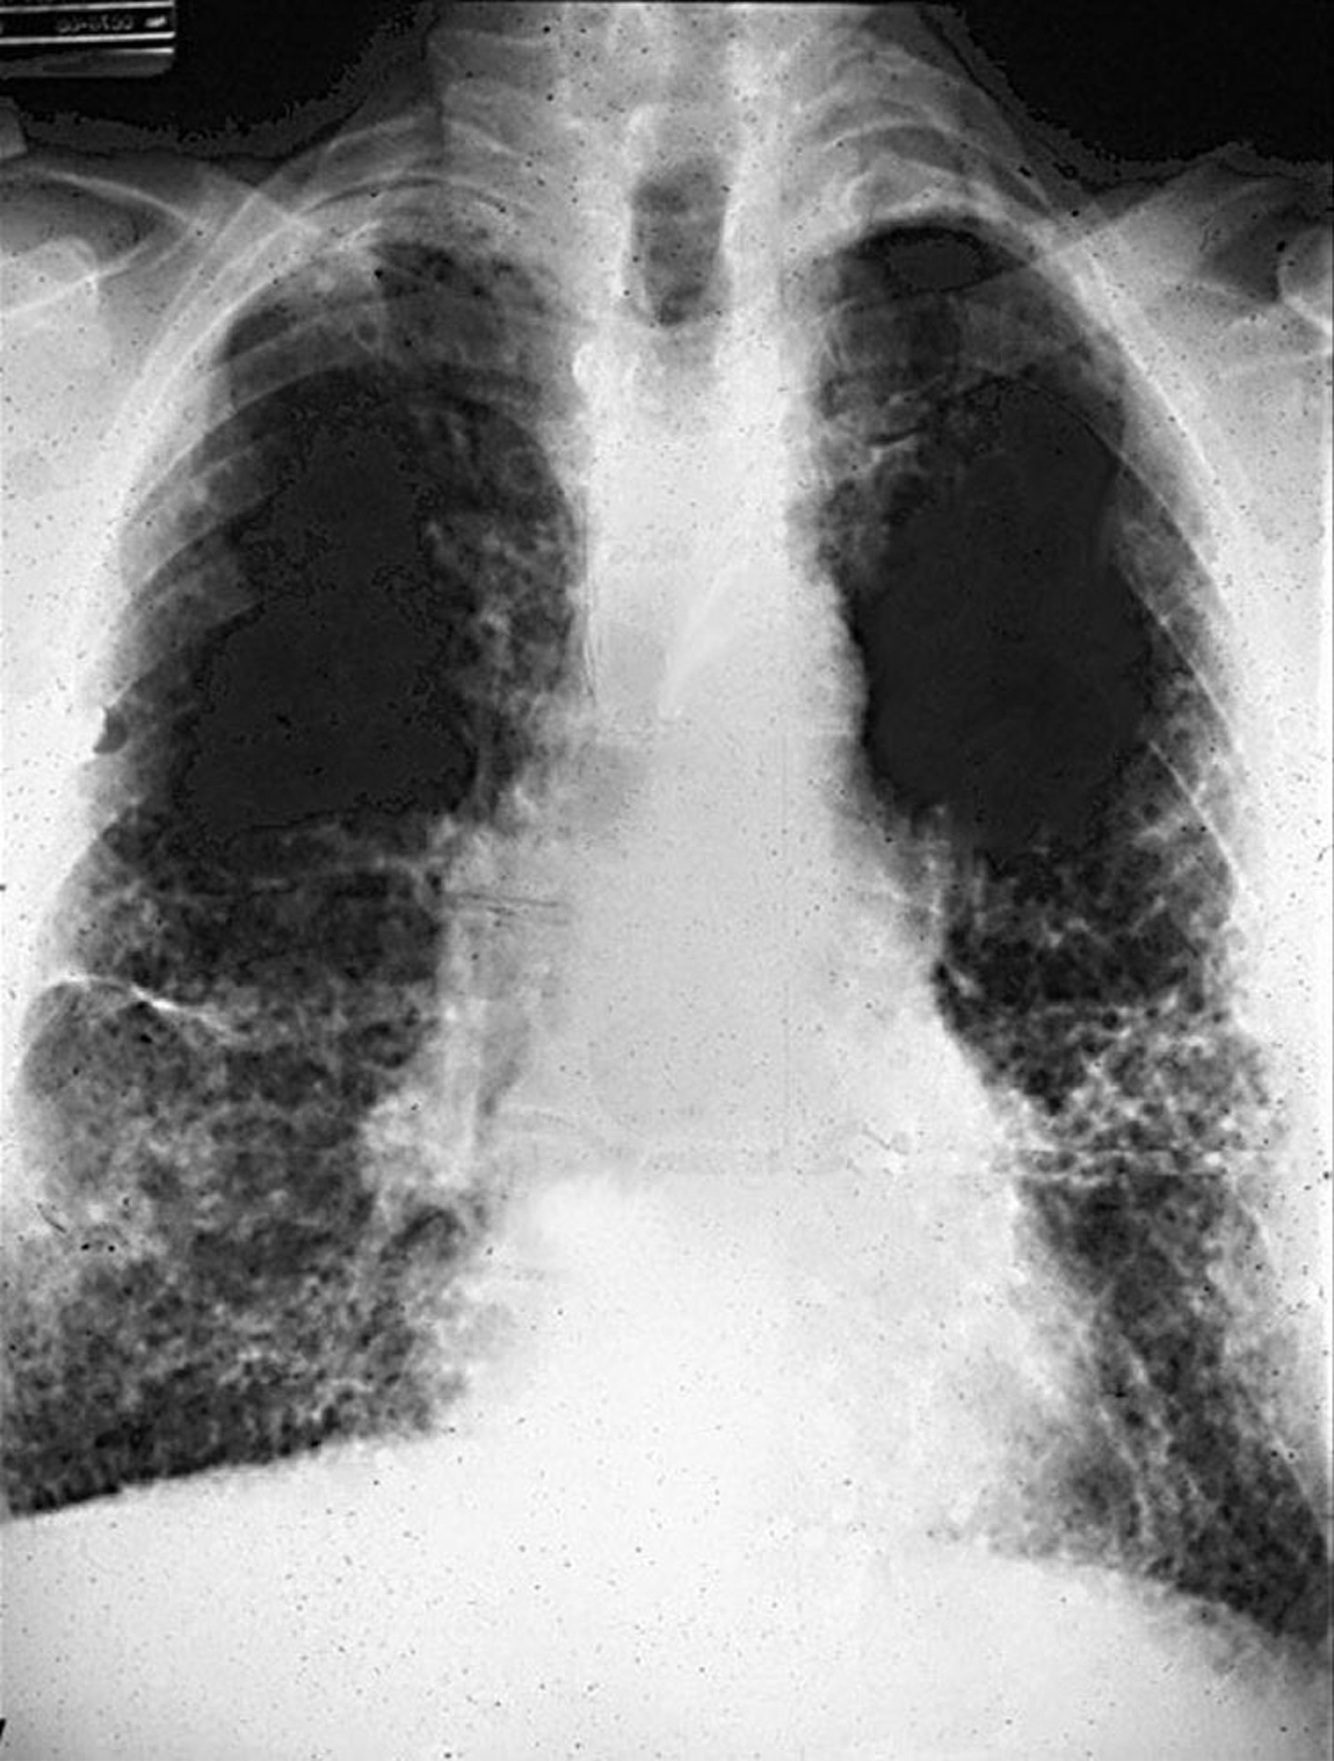

Na forma simples da pneumoconiose dos trabalhadores do carvão, as radiografias mostram pequenas opacidades nodulares entre 1-5 mm, podendo ser reticulares ou reticulonodulares. Verdadeiro ou falso?

Verdadeiro. ## Footnote A forma simples da doença é caracterizada por pequenas opacidades nodulares (1-5 mm), ocasionalmente associadas a opacidades reticulares ou reticulonodulares, visíveis na radiografia de tórax.

A forma complicada da pneumoconiose dos trabalhadores do carvão é caracterizada por grandes opacidades representando fibrose maciça progressiva, muitas vezes associadas ao enfisema. Verdadeiro ou falso?

Verdadeiro. ## Footnote Na forma complicada, a radiografia pode revelar grandes opacidades devido à fibrose maciça progressiva (FMP), frequentemente acompanhada de enfisema, o que compromete severamente a função pulmonar.

Quais são os estágios da pneumoconiose dos trabalhadores do carvão?

• Forma simples: Presença de máculas de carvão, evolução lenta e pouco sintomática. • Forma complicada: Fibrose maciça progressiva (FMP), associada à dispneia, alterações funcionais respiratórias e letalidade aumentada. ## Footnote A forma simples geralmente não apresenta sintomas graves, enquanto a forma complicada pode levar a sérias complicações de saúde.